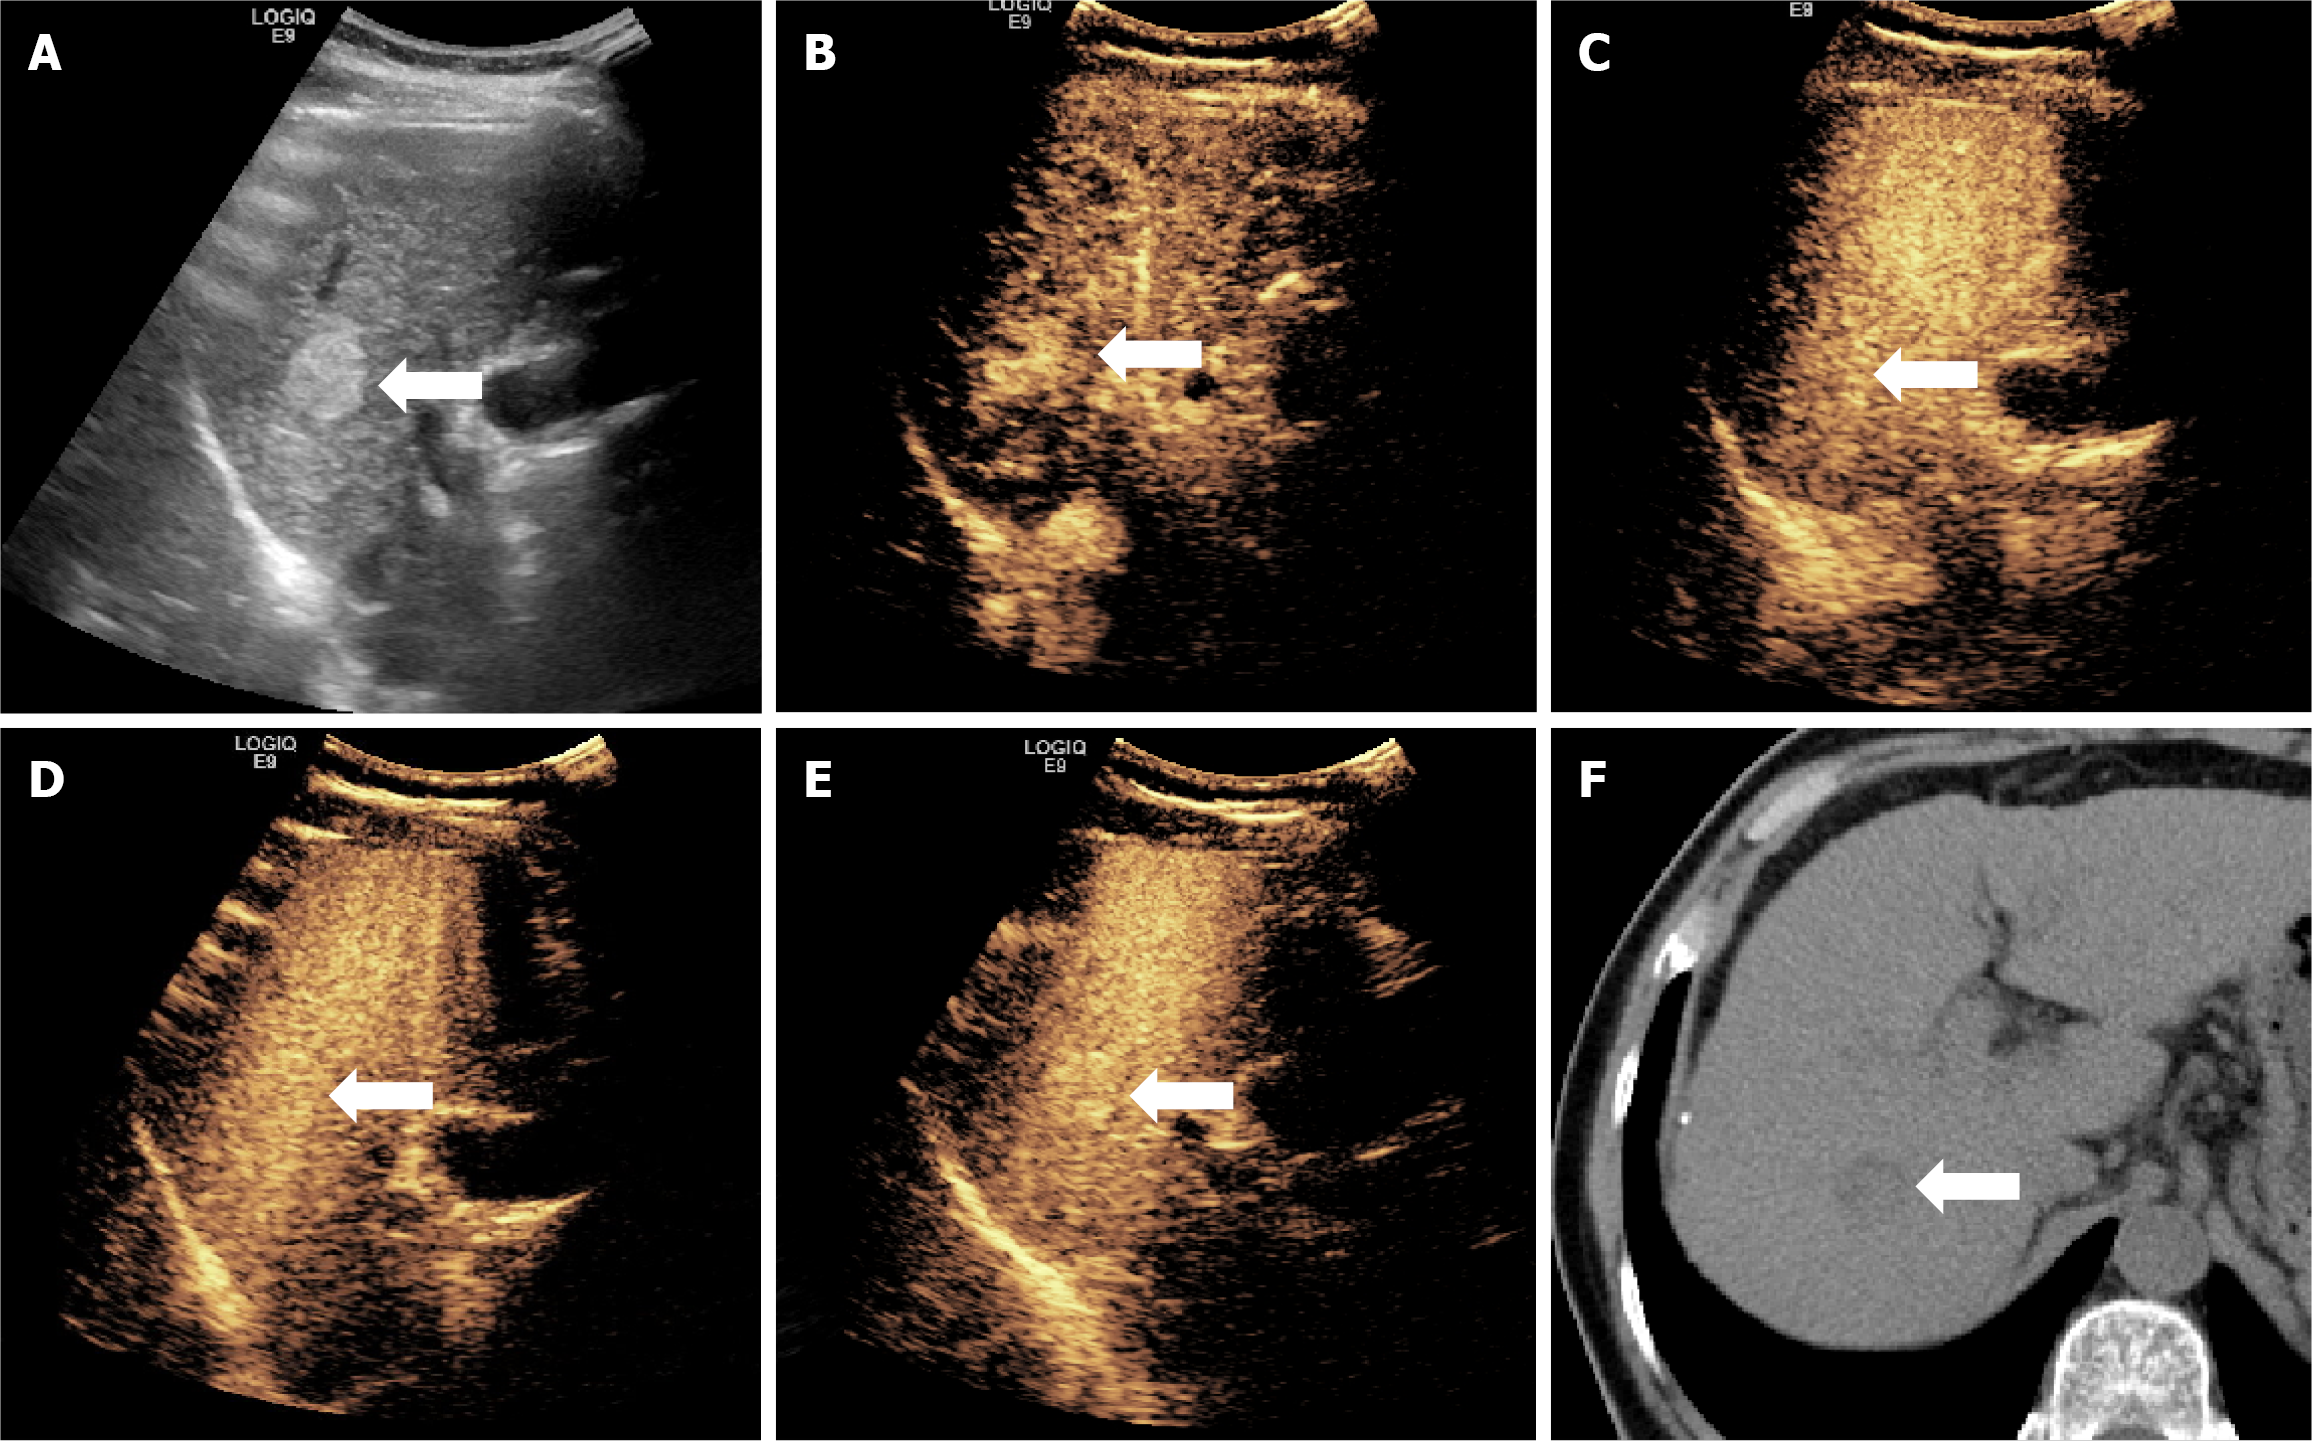

Figure 5 Ultrasound and computed tomography figures of a case of hepatocellular carcinoma showing hyper-enhancement in Kupffer phase.

A typical figure presents the case of a 57-year-old male patient with chronic hepatitis B, in whom a liver mass was detected during a physical examination. After surgical resection, pathology of the lesion revealed well-differentiated hepatocellular carcinoma without vascular invasion, and a Ki-67 LI of about 3%. A: An ultrasound image showing a mass approximately 2.1 cm in diameter located in the right lobe; B-E: Sonazoid-contrast-enhanced ultrasonography images show rapid enhancement of the mass in arterial phase, and washout does not occur in the following three phases; F: Computed tomography plain image revealing the mass.